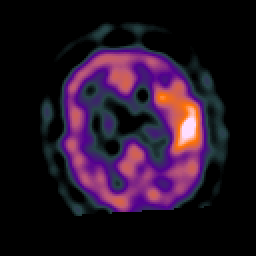

Subacute Stroke, overlay -- Slice #17

[Home][Help][Clinical] Slice 17